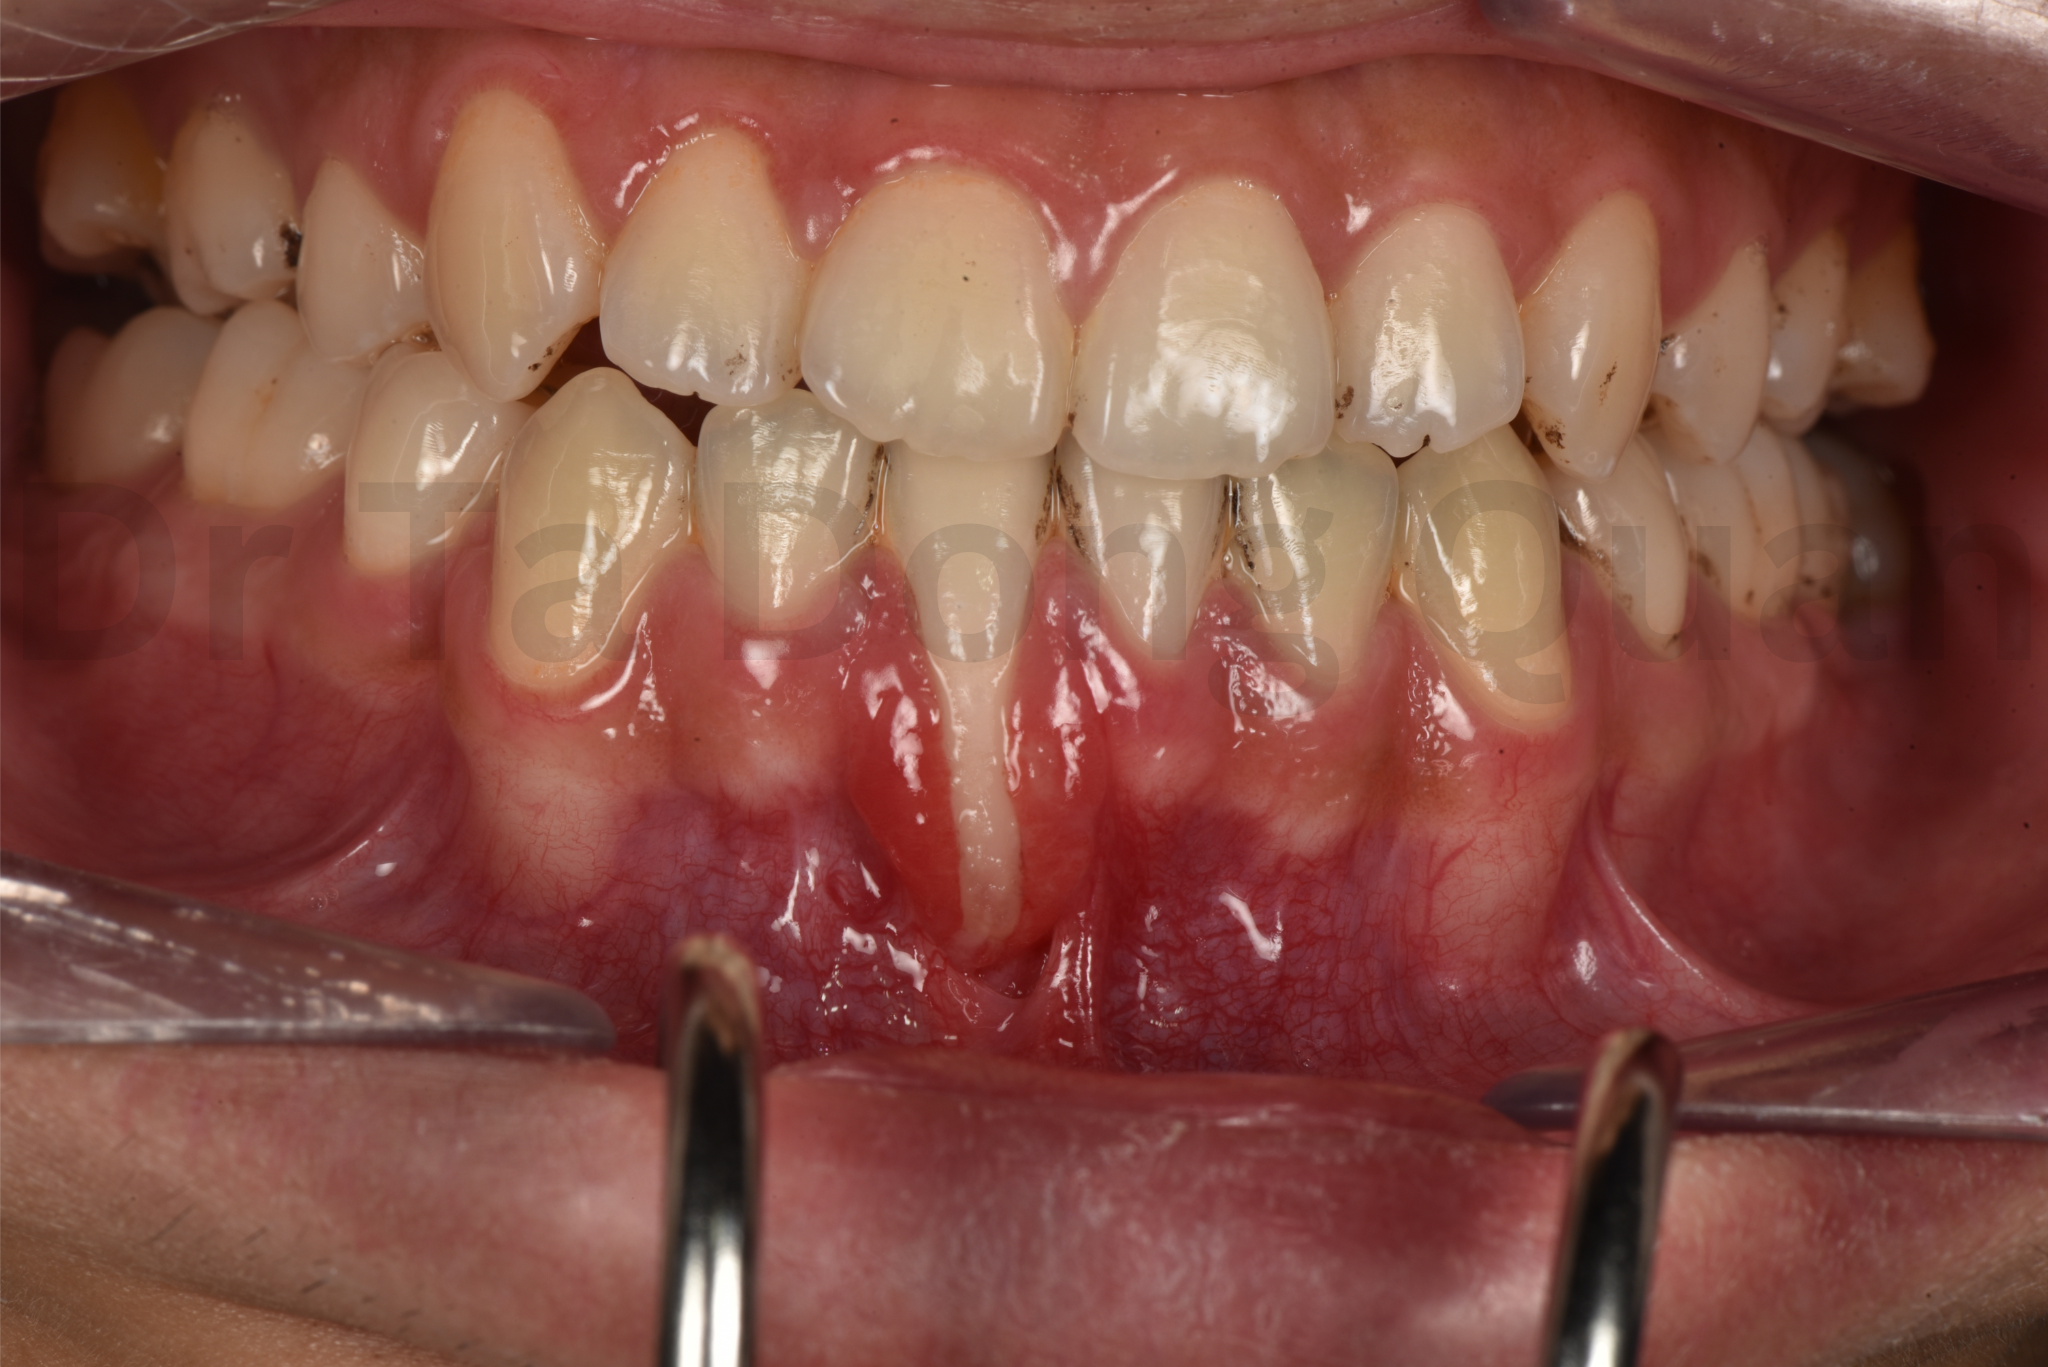

Trường hợp tụt nướu mức độ rất nặng do "hội chứng dây duy trì" sau chỉnh nha (wire syndrome)